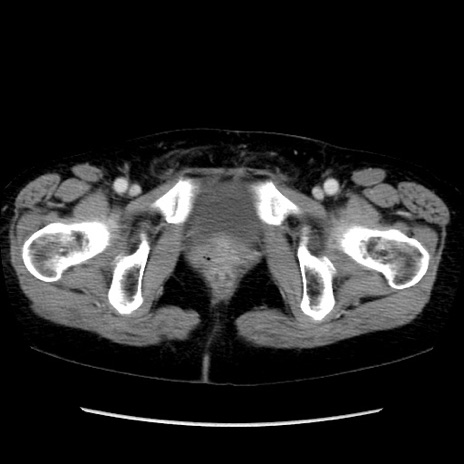

【症例】40歳代 女性

【主訴】上腹部痛、嘔気・嘔吐

【現病歴】約9時間前頃から急に上腹部痛、嘔気、嘔吐が出現。改善しないため救急要請。

【既往歴】子宮頚癌(広汎子宮全摘術、放射線療法)、腸閉塞

【身体所見】腹部:平坦、軟、腸雑音亢進、上腹部を中心に腹部全体に圧痛あり。

【データ】WBC 8400、CRP 0.03